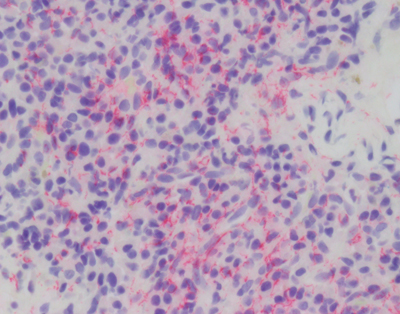

The agent Treponema pallidum (Figure 2) causes a protean complex of diseases of which its tertiary form, mediates dementia. Without antibiotic therapy, syphilis can establish a lifelong infection that evades and exhausts the immune system. Tertiary syphilis is the result of years of organism replication to the point that unfettered growth throughout the brain along with macrophage activation causes a global chronic encephalitis with neurodegeneration and dementia [5]. It is an unusual form of encephalitis, distinct from the acute viral infections described below, with little evidence of cell mediated immunity and instead a remarkable abundance of activated microglia in gray matter regions of abundant T. pallidum. As with most infections, perivascular infiltrates are prominent and with the spirochetal tropism for vascular walls can progress to an end arteritis infarctive syndrome. Histopathologic changes are widespread with minimal evidence of a system specific distribution except for a frontal/temporal cortical predominance. There is extensive neuronal loss and reactive astrocytosis but no intraneuronal protein aggregates.

Figure 2A. Warthin Starry stain of rabbit testes infected with Treponema pallidum. Short thin corkscrew like organisms (black) are seen adjacent to a small blood vessel.

Figure 2B. Immunostain (red) for T. pallidum shows a dense collection of microorganisms.